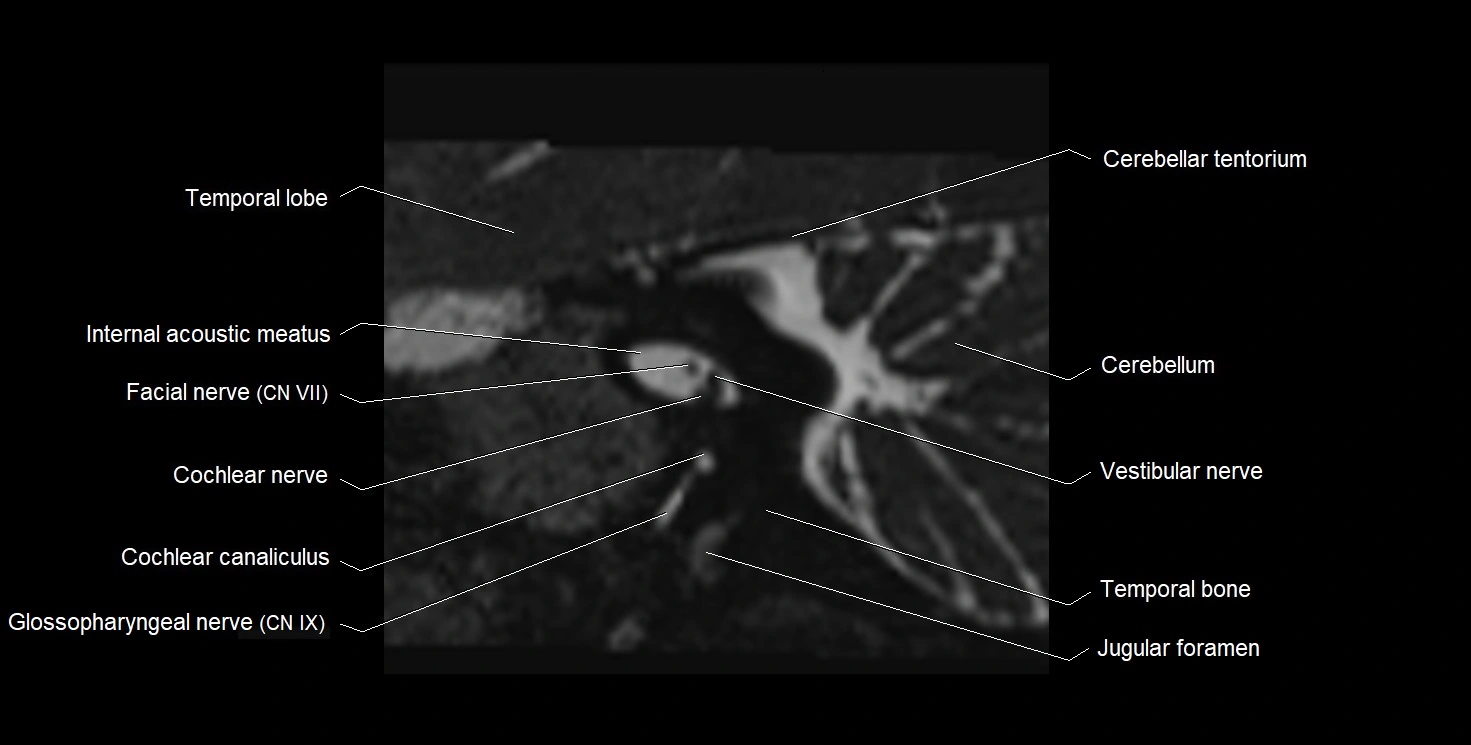

MRI images

image